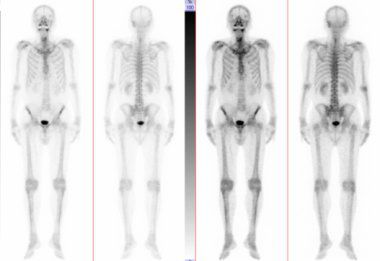

全身骨シンチグラフィ 乳癌 肺癌 前立腺癌等の骨転移病巣の検出

主な核医学検査 骨 骨シンチグラフィ 核医学検査のご案内 医療関係者

骨シンチグラフィーとは 佐賀大学病院放射線科アンオフィシャル

全身骨シンチグラフィ 乳癌 肺癌 前立腺癌等の骨転移病巣の検出

骨シンチグラフィによる骨転移の診断 Bone Scan Ct Mri画像診断